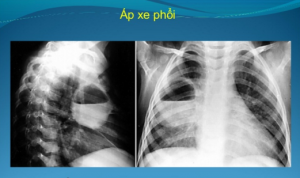

Áp xe phổi

- X-quang phổi: hang thường có thành bền vững, xuất hiện hội chứng hang, hội chứng đông đặc 1 hoặc 2 bên

- X-quang phổi nghiêng: xác định được vị trí áp xe, để chọn phương pháp dẫn lưu phù hợp

X-quang:

- Giai đoạn 1: ổ mủ kín thường thấy 1 bóng mờ, rộng, viền mờ, chưa cosoor nào bị phá hủy

- Giai đoạn 2 và 3: xuất hiện nhiều hang tròn, bờ rõ, dày, xung quanh là tổ chức phổi, bên trong có chứa khí lẫn nước